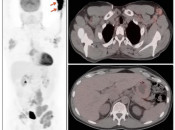

The “Sponge Effect”

Describes the common phenomenon whereby circulating FDG available for tumoral uptake is decreased due to excessive FDG uptake in non-target tissues.

This “Sponge Effect” (soaking up of available FDG by non-target tissues) leads to false negative assessment of tumors — decreasing both visual appreciation and SUV assessment of lesions.

The most common etiologies for this phenomenon include:

- Poor Patient Preparation (non-fasting state, vigorous exercise, insulin administration) [Fig. 1]

- FDG Extravasation [Fig. 2]

- Extensive Brown Fat Activity

- Metformin-Induced Bowel Uptake [Fig. 3]

- Marked Reactive Marrow Uptake

- Extensive Tumor Uptake [Fig. 4] [Fig. 5]

In each of these situations, excessive non-target uptake of FDG decreases available FDG uptake by tumors in the body.

The left MIP image demonstrates marked skeletal muscle uptake due to vigorous exercise the morning of the exam. The excessive muscle activity results in decreased available FDG for uptake throughout the remainder of the body (“Sponge Effect”), as evidenced by an abnormally low liver SUV. The one year follow up exam (right images) demonstrates a normal liver SUV, after proper patient preparation.